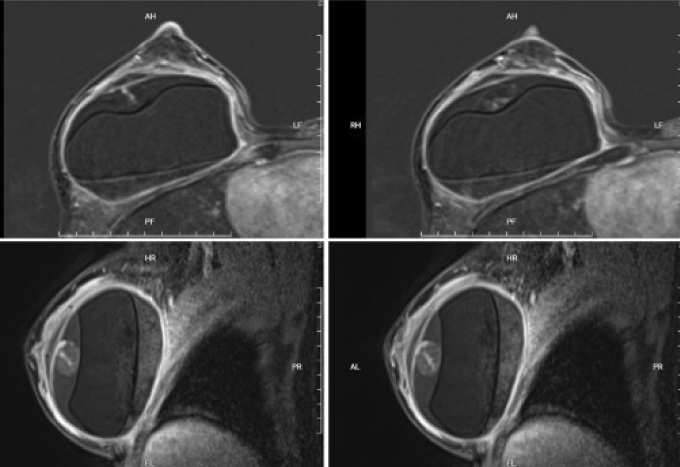

Bà Thành nâng ngực cách đây 15 năm, không có bất thường về mạch máu, gần đây không va chạm gì ảnh hưởng đến ngực. Khi cơn đau ngực tăng nặng, bà đến Bệnh viện Đa khoa Tâm Anh TP HCM kiểm tra. Kết quả chụp cộng hưởng từ (MRI) của bà Thành cho thấy túi ngực hai bên còn nguyên vẹn, ngực bên trái có tụ dịch không thuần nhất quanh túi ngực. Chọc hút kim nhỏ cho thấy có dịch viêm, không phát hiện tế bào ung thư hay di căn.

Tương tự, bà Thắm, 51 tuổi, đau ngực phải kéo dài, biến dạng ngực một bên. Bà cũng từng nâng ngực 10 năm trước. Khi đến Bệnh viện Đa khoa Tâm Anh TP HCM khám, ngực phải bà Thắm có dấu hiệu căng tức, biến dạng, bác sĩ nghi ngờ co thắt bao xơ túi ngực, vỡ túi ngực. Kết quả MRI phát hiện vỡ túi hai bên kèm tụ máu quanh, silicone rò ra mô xung quanh. Trong khi mổ, êkíp phẫu thuật hút khoảng 200 ml hỗn hợp máu và silicone, xử lý bao xơ, thay túi độn mới.